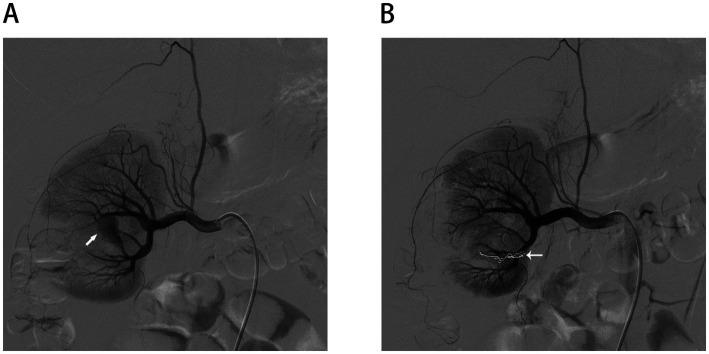

Renal epidermoid cysts (RECs) are exceedingly rare benign cystic lesions, with only 15 histologically confirmed cases reported worldwide to date. Due to their non-specific clinical and radiological features, they are often misdiagnosed preoperatively as infectious or neoplastic conditions. Here, we report a 25-year-old man in whom a complex renal cyst was incidentally identified during a routine health examination. Retrospectively, the patient reported mild urinary frequency and low-grade fever. Imaging suggested a non-enhancing heterogeneous cyst in the lower pole of the right kidney. Laparoscopic partial nephrectomy was performed, revealing abundant yellow-white caseating material intraoperatively, prompting empirical anti-tuberculosis therapy in the context of regional endemicity. However, histopathological analysis confirmed a diagnosis of RECs, and anti-tuberculous treatment was subsequently withdrawn. On postoperative day 5, the patient developed gross hematuria due to a renal artery pseudoaneurysm, which was successfully managed with selective arterial embolization. This case highlights the diagnostic challenges posed by atypical cystic renal lesions and underscores the importance of integrating imaging, intraoperative findings, and histopathology. Including RECs in the differential diagnosis may prevent unnecessary antituberculous therapy and overtreatment.

肾表皮样囊肿(RECs)是极其罕见的良性囊性病变,迄今为止全球仅报告了15例经组织学确诊的病例。由于其非特异性的临床和影像学特征,它们在术前常被误诊为感染性或肿瘤性疾病。在此,我们报告一名25岁男性,其在常规健康检查中偶然发现一个复杂肾囊肿。回顾性分析,患者自述有轻度尿频和低热。影像学检查显示右肾下极有一个无强化的不均匀囊肿。实施了腹腔镜部分肾切除术,术中发现大量黄白色干酪样物质,鉴于当地的地方病情况,给予经验性抗结核治疗。然而,组织病理学分析确诊为肾表皮样囊肿,随后停用抗结核治疗。术后第5天,患者因肾动脉假性动脉瘤出现肉眼血尿,通过选择性动脉栓塞成功处理。该病例凸显了非典型囊性肾病变带来的诊断挑战,并强调了综合影像学、术中发现和组织病理学的重要性。将肾表皮样囊肿纳入鉴别诊断可避免不必要的抗结核治疗和过度治疗。